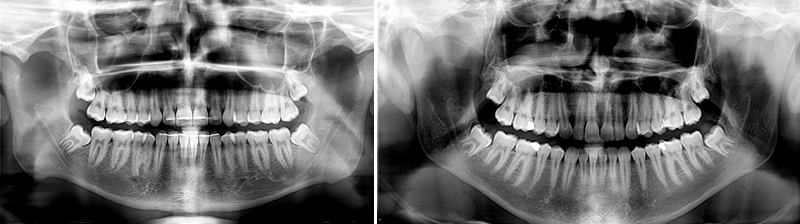

Une radio panoramique est réalisée pour visualiser le nombre, la position des dents, le degré d’inclusion la forme et la longueur des racines ainsi que le nerf alvéolaire inférieur.

Pour débuter, il est préférable que les dents soient sous muqueuses, les racines soient en cours d’édification et les nerfs alvéolaires Inférieurs (NAI) à distance.

Par exemple dans les 2 situations cliniques suivantes :

Parfois, il est préférable de s’abstenir surtout en l’absence de symptôme et de recontrôler l’année suivante.

Sur la radiographie ci-dessus, les dents sont complétement incluses et asymptomatiques, l’extraction n’est pas indiquée.